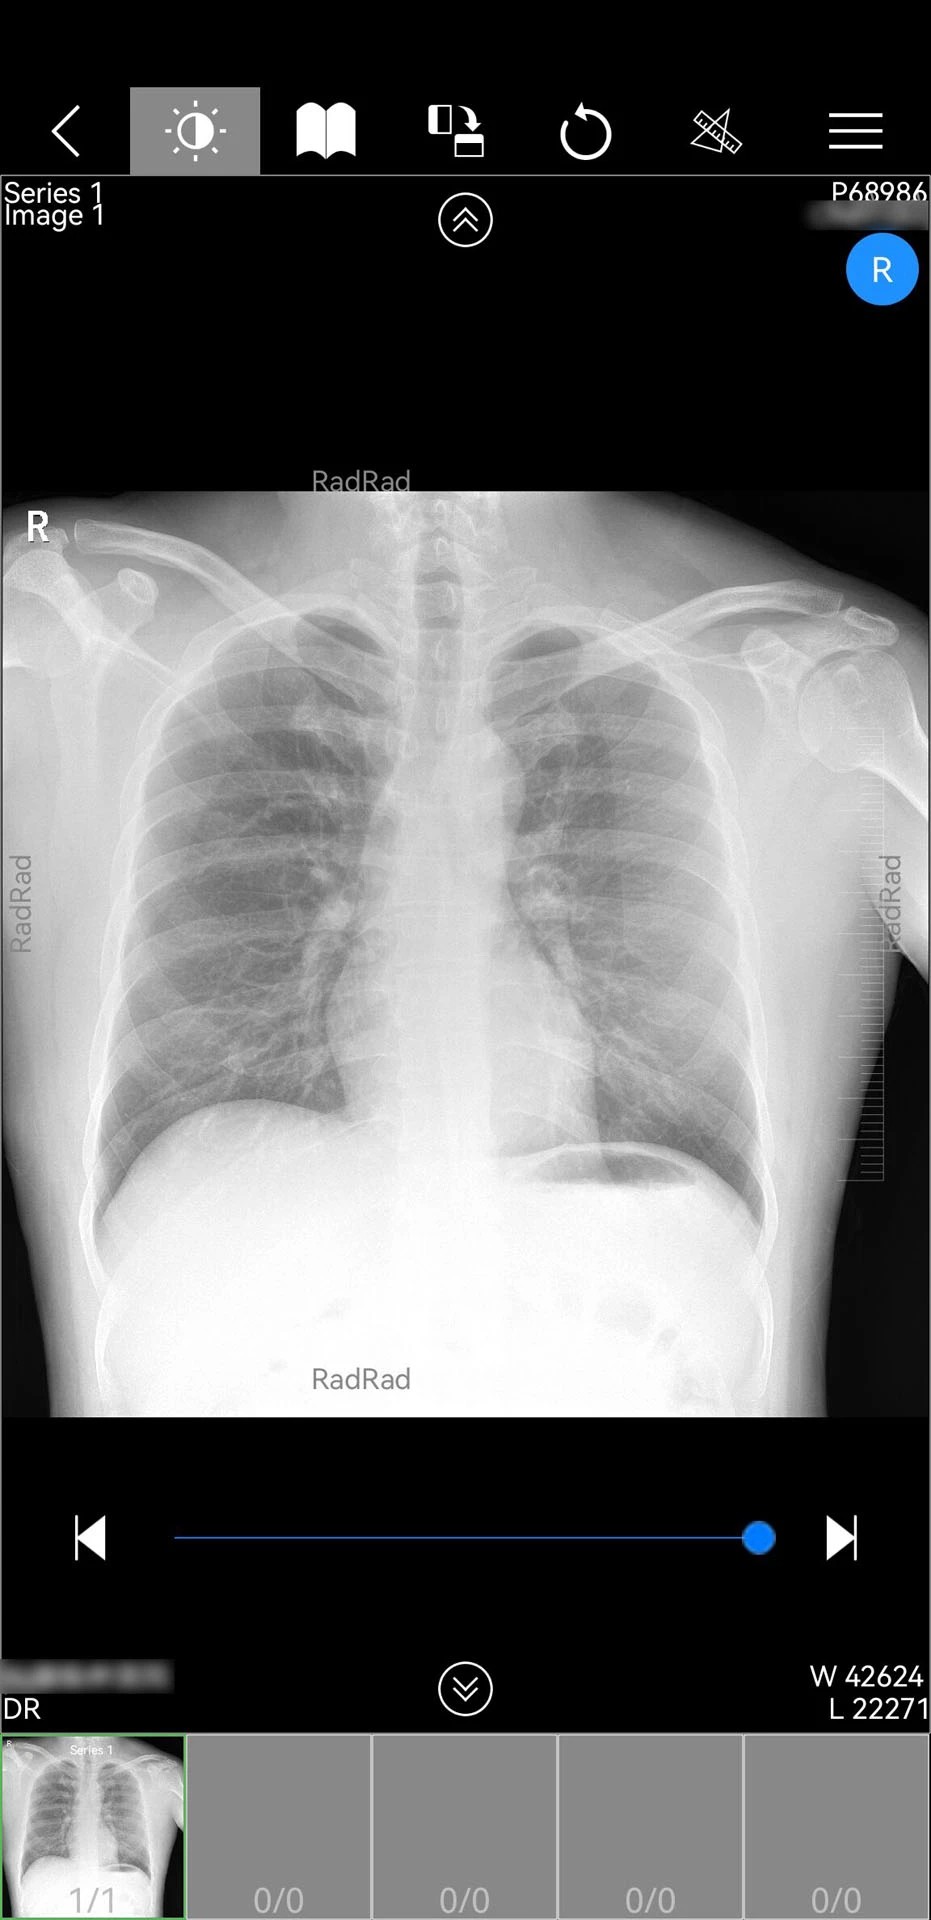

2. 多模态影像调阅:集成DICOM影像解析技术,可实时加载CT、MRI、X光等检查数据,支持三维重建与多平面重组。在2025年2月更新的1.18.110版本中,新增CT三维处理服务,使医生能直接在移动端完成肺结节体积测量等精细操作。

2. 极简操作体验:全中文可视化界面适配移动端手势操作,医生可通过双指缩放、滑动切换等动作快速浏览影像序列。2025年7月iOS端更新后,云影像界面加载速度提升40%,单次调阅耗时从3.2秒缩短至1.9秒。

3. 智能辅助诊断:内置AI影像分析引擎,可自动识别肺结节、乳腺钙化点等常见病变,生成结构化报告供医生参考。在2024年12月的测试中,AI对肺结节的检出准确率达92.3%,与资深放射科医生诊断结果吻合度超过85%。